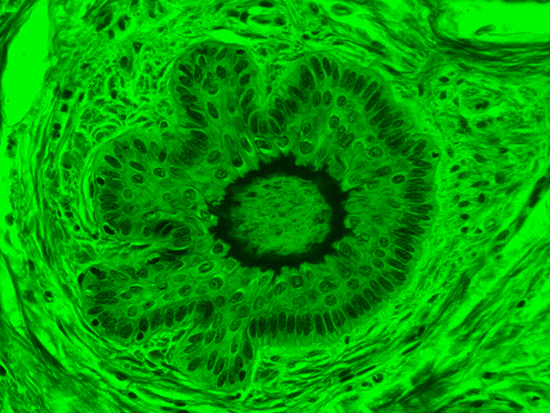

Masson's trichrome stain is incredibly effective in differentiating cells and their components from the surrounding connective tissues. One of the most common stain types, which has been used on the dermal tissue sample seen in the images within this article, yields a number of colors where cell nuclei appear dark red, collagen and other tissues appear green or blue, and cell cytoplasm appear red/purple (Jones, 2010). These stains have been imaged under brightfield and darkfield illumination, and then again with specific filters to selectively focus on the cellular constituents of the epidermis. The primary application for the epidermal trichrome stains is differentiating healthy collagen and muscles from connective tissues onset with tumorigenesis. Typically the tumors proliferate from muscle cells and fibroblasts deep in the dermal tissue (Blitterswijk, 2010).

Figure 3: Brightfield Image of Dermal Tissue filtered with Green

When comparing Figure 3 with Figure 4, there is once again a significant visual difference. The most obvious feature is the change in color from green to red due to a different hardcoated filter being positioned in the optical path. The less obvious difference is the varying contrast levels caused by the filters at specific regions of the dermal tissue. For example, Figure 3 exhibits a distinct ring at the central region of the cell with additional matter within. In Figure 4, the ring is extremely faint and the internal matter is not visible. With that said, the cell and surrounding dense materials are more evident in Figure 3, whereas the muscle fibers and collagen are more pronounced in Figure 4.